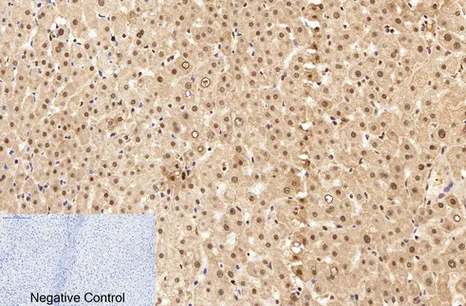

MDM2 Rabbit Polyclonal Antibody

Cat: APRab13758

Cdc25B Rabbit Polyclonal Antibody

Cat: APRab08505